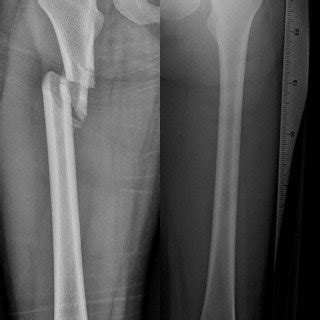

Subtrochanteric fractures are fractures of proximal femur below lesser trochanter. The 7th character should be used when the.

The 7th character should be used when the. Most subtrochanteric fractures treated with im nail. Hip fractures include femoral neck, intertrochanteric or subtrochanteric fractures, and the classification is based on their location.

This resource is to assist in the understanding of the classification system utilized in. To code a diagnosis of this type, you must use specify a 7th character that describes the diagnosis 'displaced subtrochanteric fracture of right femur' in more detail. Twelve subtrochanteric/diaphyseal fractures (4%) were found in 10 subjects, 3 of whom had not received bps. This resource is to assist in the understanding of the classification system utilized in. Hip fractures are very dangerous episodes especially for elderly and frail patients. Subtrochanteric fractures are fractures of proximal femur below lesser trochanter. Below are 45 working coupons for icd 10 code for displaced intertrochanteric fracture from reliable websites that we have updated for users to get. Proximal fragment is typically externally rotated and flexed due to the pull of the iliopsoas (iliacus/ psoas) and abducted by the short abductors inserting into the greater trochanter. Subtrochanteric fractures occur between the lesser trochanter and the proximal 5cm of the femoral shaft, often associated with an intertrochanteric fracture. Which of the following reduction forces must be applied to the proximal fragment to. Subtrochanteric region is typically defined as the area from lesser. Levine fractures of the subtrochanteric region of the proximal femur can be especially challenging to manage, and they warrant special consideration to obtain consistently satisfactory results. M84.551a fracture, pathological (pathologic), due to neoplastic disease, femur c79.51 carcinoma (malignant), metastatic, see neoplasm, secondary. Hip fractures include femoral neck, intertrochanteric or subtrochanteric fractures, and the classification is based on their location. A total of 10,548 entries fulfilling the inclusion criteria were identified in the register and included in the study. Extracapsular fractures include intertrochanteric (between the trochanters) and subtrochanteric (distal to the trochanters). Most subtrochanteric fractures treated with im nail.